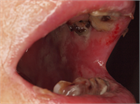

概要・推奨

1. 化学療法による口内炎の予防として、柔らかい歯ブラシで1日2回以上歯を磨き、毎日デンタルフロスを使用し、生理食塩水や重曹、水道水などの低刺激の溶液で1日4回以上口をすすぐことが推奨される(推奨度1)

1. 頭頚部腫瘍に対する化学放射線療法の症例に対して、口腔内に低出力レーザーを照射すると、口内炎が改善できる可能性がある(推奨度2)

1. フルオロウラシル投与前に口の中に氷片を30分入れておくこと(cryotherapy)は、口内炎の重症化を低減できる(推奨度2)